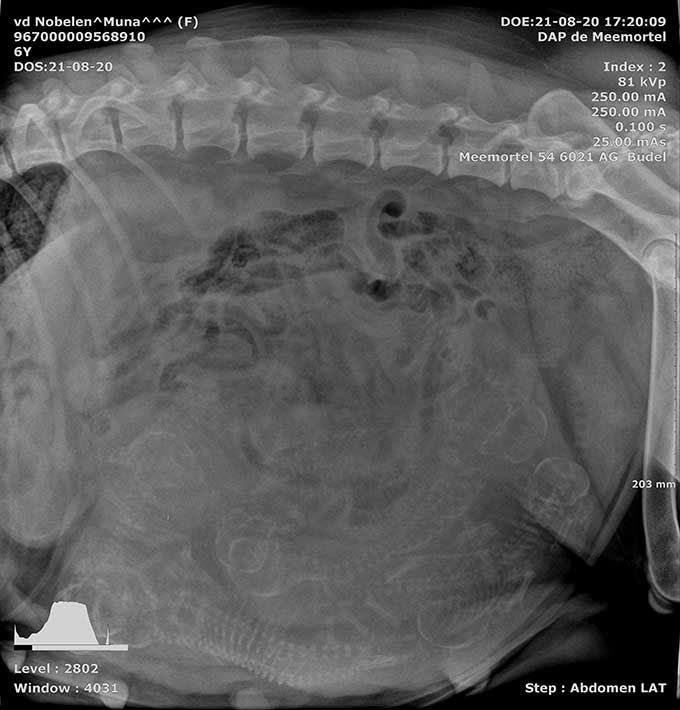

Muna 't Hupke HD A ED vrij |